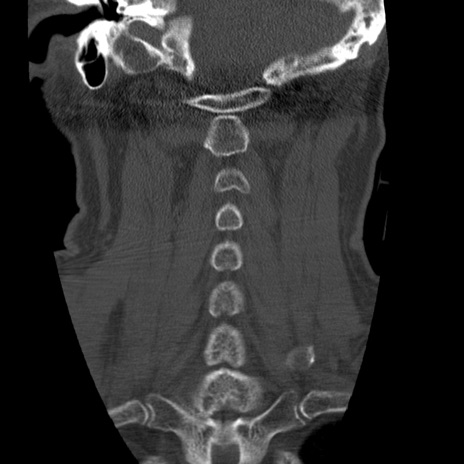

症例50 頚椎CT(冠状断像)

横断像